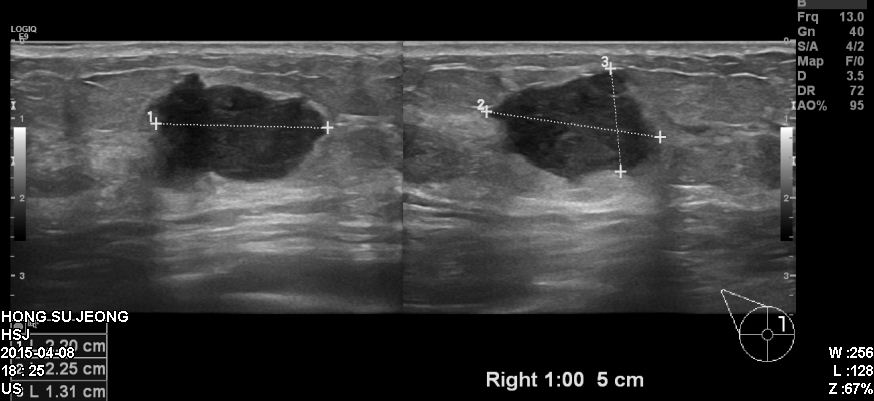

우측유방에 만져지는 멍우리로 내원하신 50대 환자분이십니다.

본원에서 유방초음파 시행후 우측유방 1시방향에 확인되는혹 조직검사 시행하였고

결과상 침윤성유관암진단되었습니다.